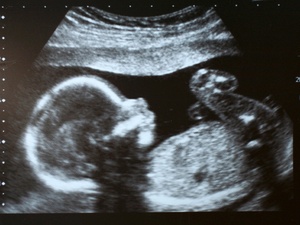

Só descobri a gravidez em agosto do ano passado, porque fui a uma gastroenterologista e ela pediu uma ultrassonografia do intestino. Eu já estava com 30 semanas, aproximadamente 7 meses.

Foi somente ao voltar pela terceira vez que o médico me pediu uma ultrassonografia nos rins, e ali descobri que estava grávida. O médico ainda disse que a gravidez já estava avançada, mas não tinha como ter a precisão de tempo.